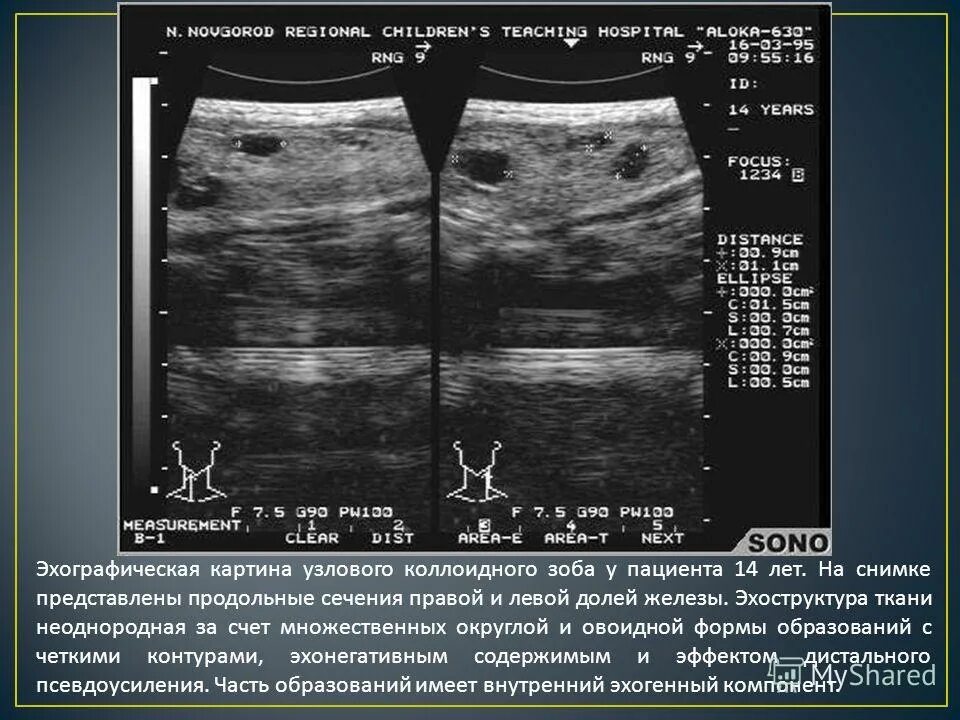

Диффузно неоднородно что значит